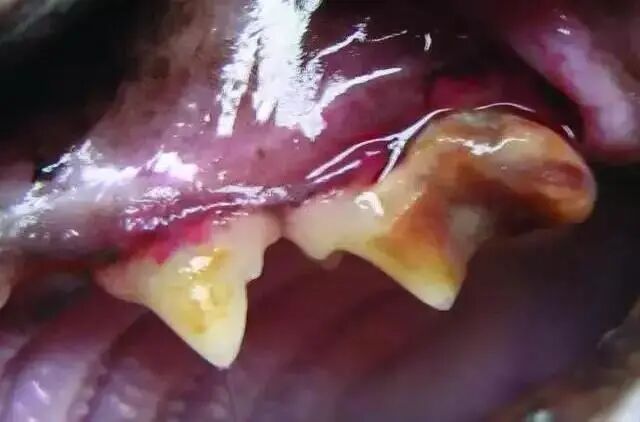

3级

牙吸收病影响到牙髓腔, 出现髓腔吸收